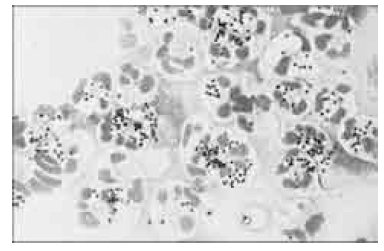

Com base na figura acima, que mostra microrganismos juntamente com células humanas, julgue os itens a seguir, acerca dos diversos testes utilizados em microbiologia.

Staphylococcus aureus são cocos esféricos catalase positivos que costumam se apresentar em grupos, de forma semelhante aos mostrados juntamente com neutrófilos na figura.